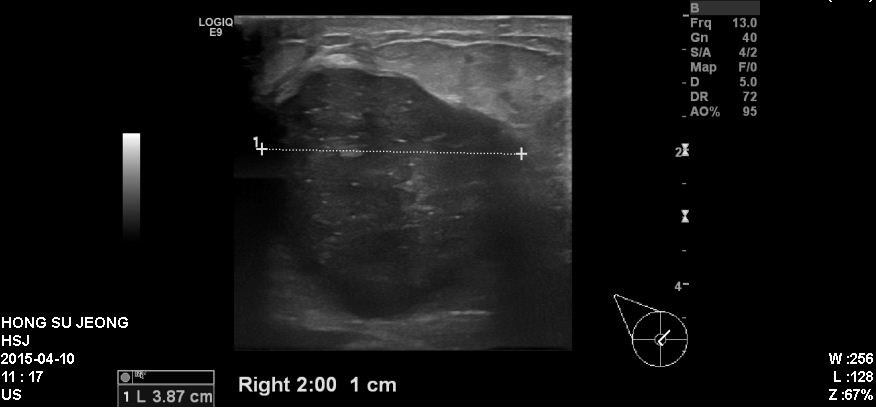

우측유방에 만져지는 멍우리로 내원하신 60대 환자분이십니다.

본원에서 우측유방 2시방향에 혹과 우측겨드랑이를 각각 조직검사와 세침검사 시행하였고

결과상 침윤성유관암으로 진단되었습니다.